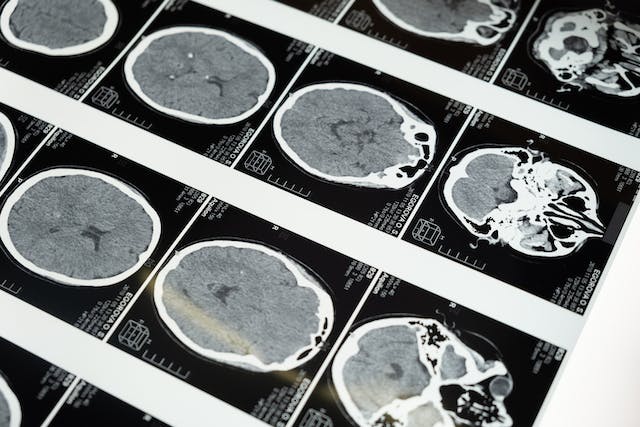

- 영상 진단 검사: MRI, CT, PET 등의 영상 진단 검사를 통해 뇌의 구조적 이상을 찾아낼 수 있습니다. 이러한 검사는 뇌의 손상, 종양, 뇌혈관 이상 등을 확인하는 데 도움이 돼요.